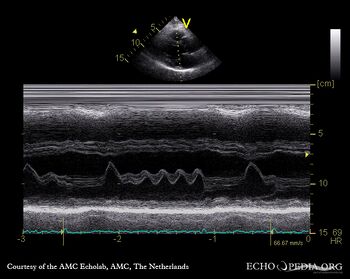

Atrial flutter at M-Mode

M-Mode through mitral valve in patient with atrial flutter